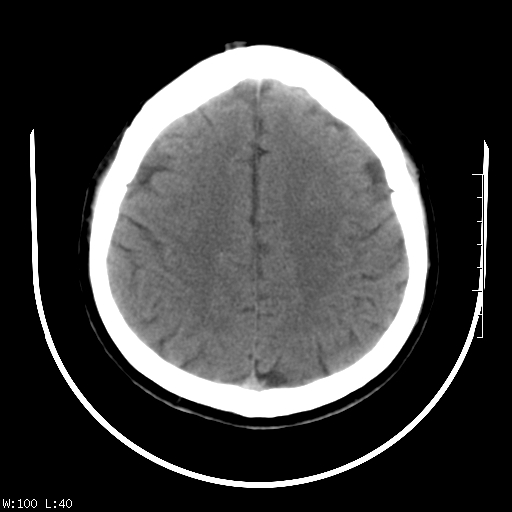

标题: CT22236:男,45,经常头痛。看看脑干正常吗? [打印本页]

标题: CT22236:男,45,经常头痛。看看脑干正常吗?

未见明显异常,建议ct增强或mri检查。

没见异常密度及形态改变啊,我认为是正常的。

颅脑ct轴位平扫颅内未见明确异常。

颅脑ct平扫未见明确异常,必要时mri检查。

颅脑ct平扫未见异常